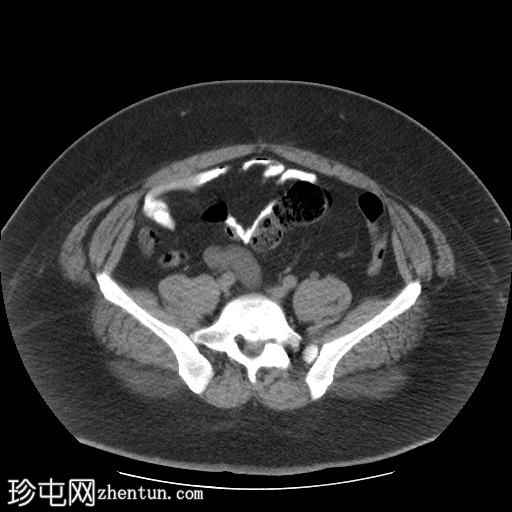

轴位肾排泄期

右肾集合系统完全重复。上肾集合系统的输尿管异位开口于前列腺尿道,导致上游集合系统显著扩张。这引起肾实质的慢性改变,包括上肾组织变薄和上肾盏排尿功能障碍。

相反,右肾下肾集合系统的输尿管位置正常,无扩张或结石迹象。

左肾和输尿管外观正常。

右肾重复畸形伴异位输尿管的CT表现。异位输尿管是一种先天性异常,指输尿管在异常位置开口于膀胱。

男性异位输尿管可连接至膀胱下段、尿道后段、精囊、输精管、射精管,或极少数情况下连接至直肠。